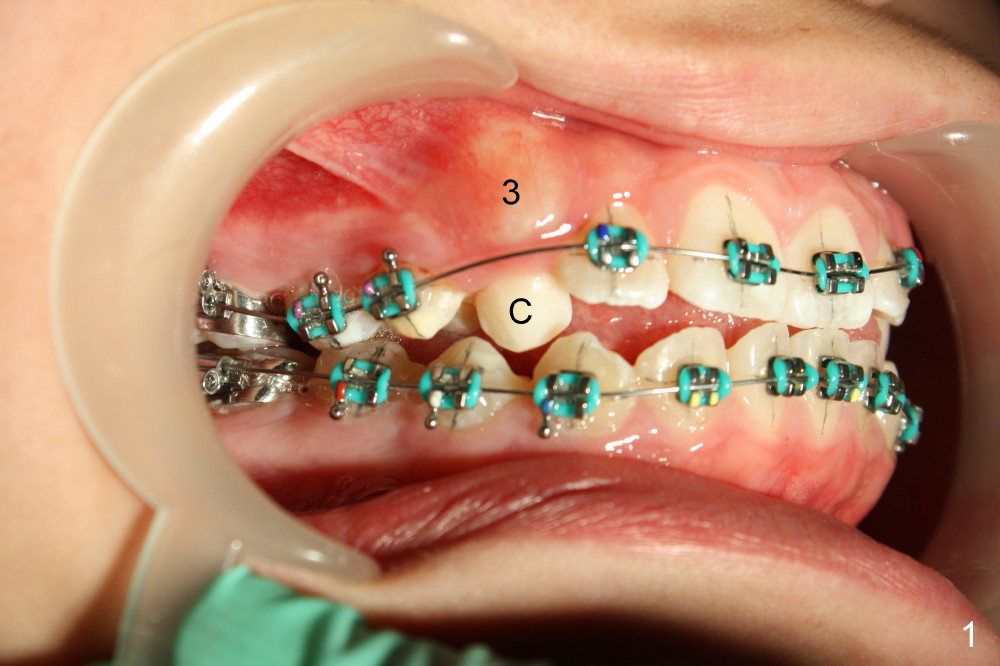

Treatment plan for Nathalie (12 years 9 months old) after banding & bracketing (Visit 1 (Fig.1-3, 7 and 8): use 14 niti)

2. On bracketing, u1,2s are not level (upper central and lateral incisors, Fig.2).  On Visit 2, 3 or later, they are expected to be at the same level

3. Pre-operatively, the upper and lower anterior teeth edge to edge (Fig.3: u1 vs. l1).  Do we need to add composite on posterior occlusal surfaces for the upper anteriors to move labially?  To be decided on Visit 2